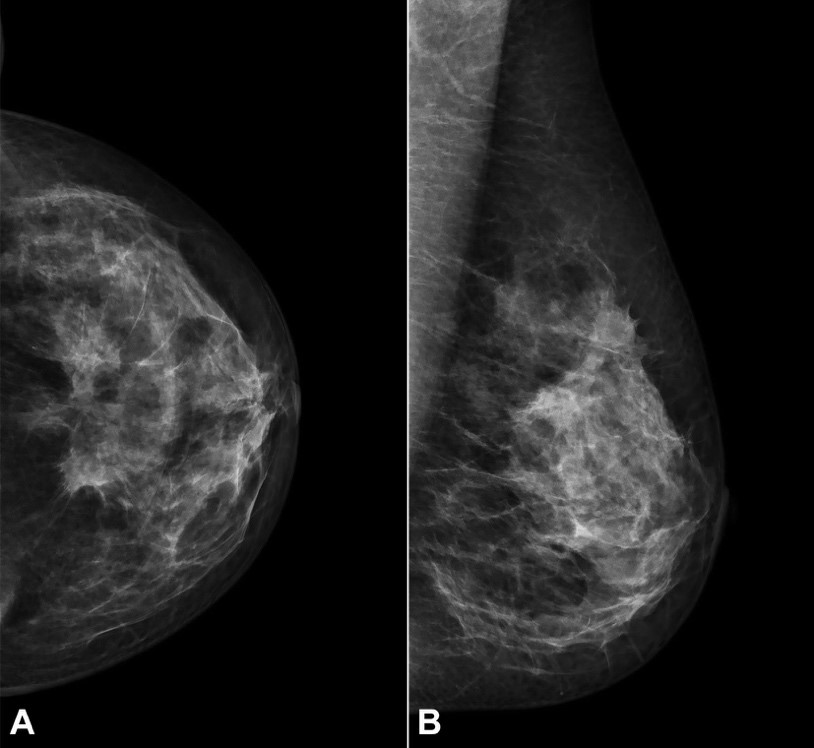

The mammography described a heterogeneously dense breast pattern with a solid irregular lesion with 50x26 mm in the upper outer quadrant of the left breast (Figure 1A, B).

After completion of 3 cycles, a bilateral mammogram and an abdominal MRI for imaging response assessment were performed. Mammography showed a nodular lesion in the upper outer quadrant of the left breast consistent with the previously identified tumor. A dimension reduction to 31x10 mm (previous: 50x26 mm) was observed, corresponding to a partial response by RECIST 1.1 Criteria1 (Figure 3).